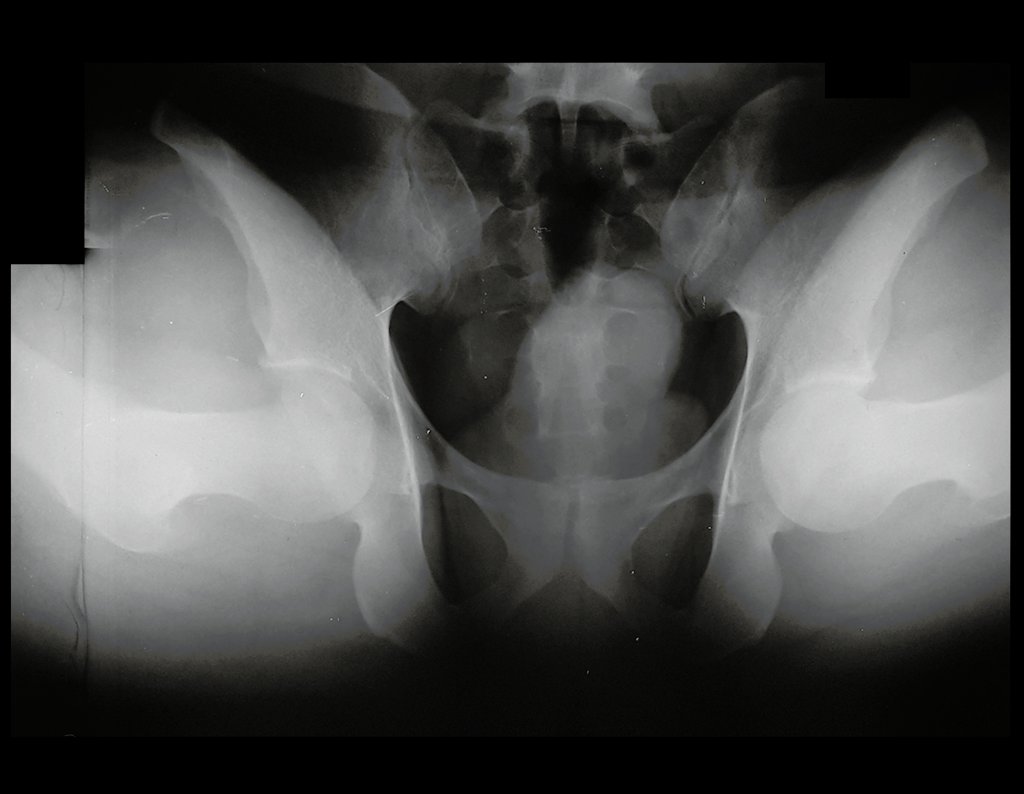

Se le realizó una resonancia magnética de columna lumbar y cadera en abril de 2015, figuras 1 a 8.

El informe de resonancia magnética de ese momento informó la hipótesis diagnóstica de osteoma osteoide.

Sin embargo, después de cuatro meses, en agosto de 2015 se realizó una artrorresonancia que infirió la posibilidad de pinzamiento femoroacetabular, figuras 9 y 10.